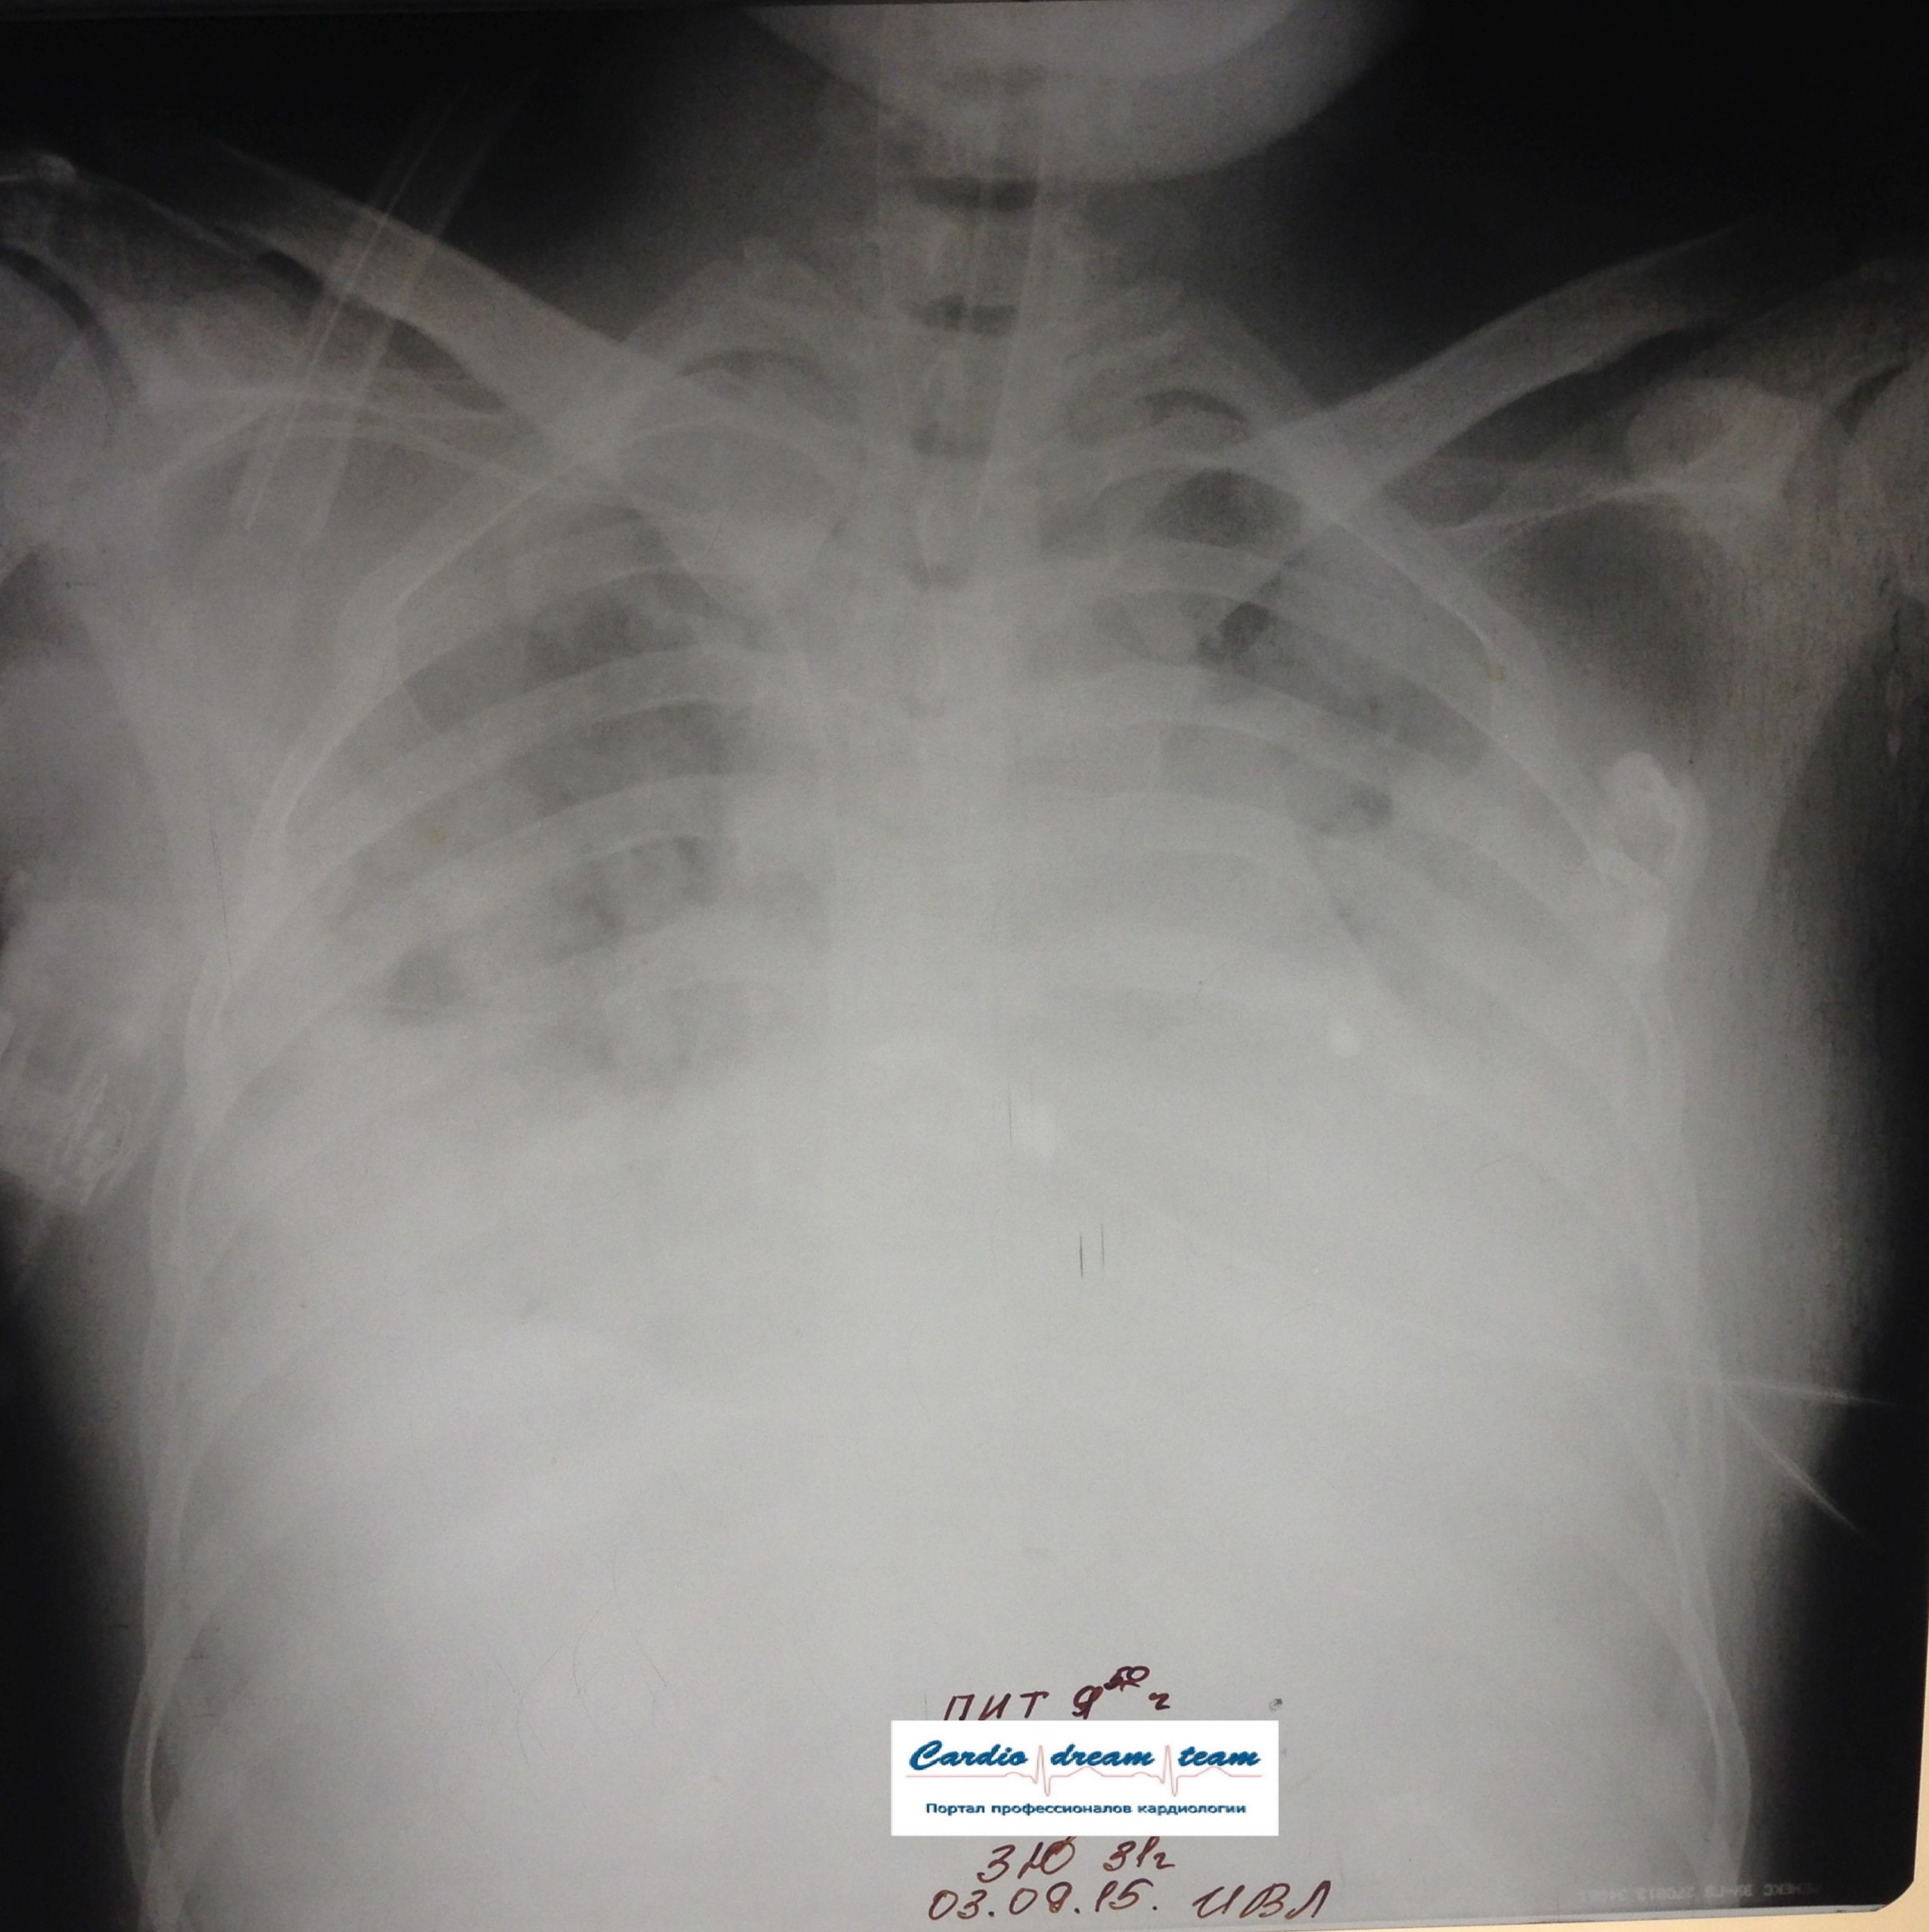

Возникновение и динамика вентилятор - ассоциированной пневмонии.

2-.jpg

2-.jpg [ 759.1 KiB | Просмотров: 53286 ]

3-.jpg

3-.jpg [ 754.54 KiB | Просмотров: 53286 ]